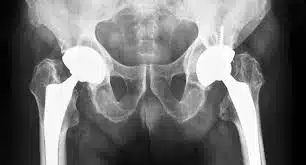

Hip replacement surgery is a procedure during which old and damaged hip joints are replaced with an artificial one (known as a prosthesis). Hip replacement is also known as total hip arthroplasty. Arthritis in the hip area can have different types, including:

The general outline of a hip replacement surgery is to remove the damaged hip and replace it with prosthesis. The hip prosthesis is usually made up of a stem that connects the pelvic bone and thigh bone. It also consists of a cup that will be inserted into the hip joint’s socket. The cup and stem are made of metals (sometimes plastic or ceramic), while the head joint is made of ceramic. Moreover, hip prostheses have two different categories: cemented and non-cemented prosthesis. A non-cemented prosthesis attached to the bone with a special surface while the cemented one will be attached using surgical cement. In non-cement prosthesis, one side enters the femoral bone canal and other side fixes into pelvic bone. Sometimes surgeons prefer to combine these two types for replacing a hip.

In total hip replacement surgery, the surgeon removes the damaged bone marrow and replaces it with a metal sphere. The artificial hip joint matches two bones together. At the top is the acetabular cavity, which is a part of the pelvis. This cavity is approximately a hemisphere. Inside the cavity of the acetabulum is the femoral head.